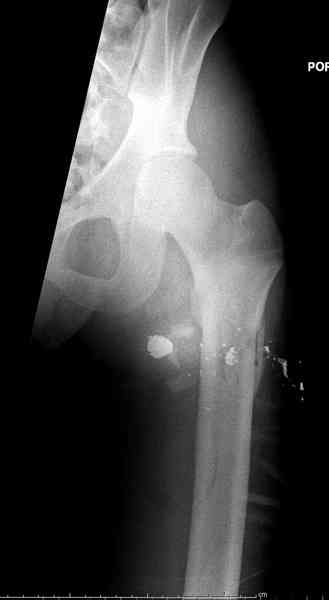

Р.S. Привожу клинический пример больного с огн. переломом бедра Густилло- Андерсон 111 А